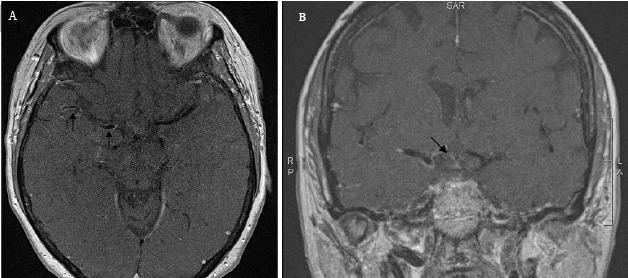

| Figure 3: Black-blood MRI demonstrates unilateral enhancement. (A) Post-contrast black blood MRI images demonstrate enhancement of the right MCA (black arrows) and (B) of the right ACA (black arrow).Black-blood MRI demonstrates unilateral enhancement. (A) Post-contrast black blood MRI images demonstrate enhancement of the right MCA (black arrows) and (B) of the right ACA (black arrow). |